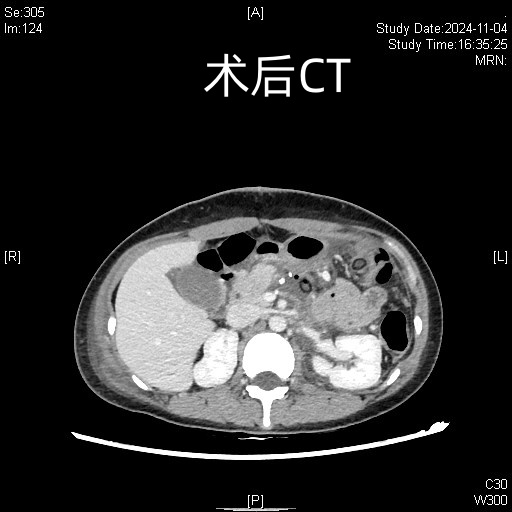

术前术后对比图